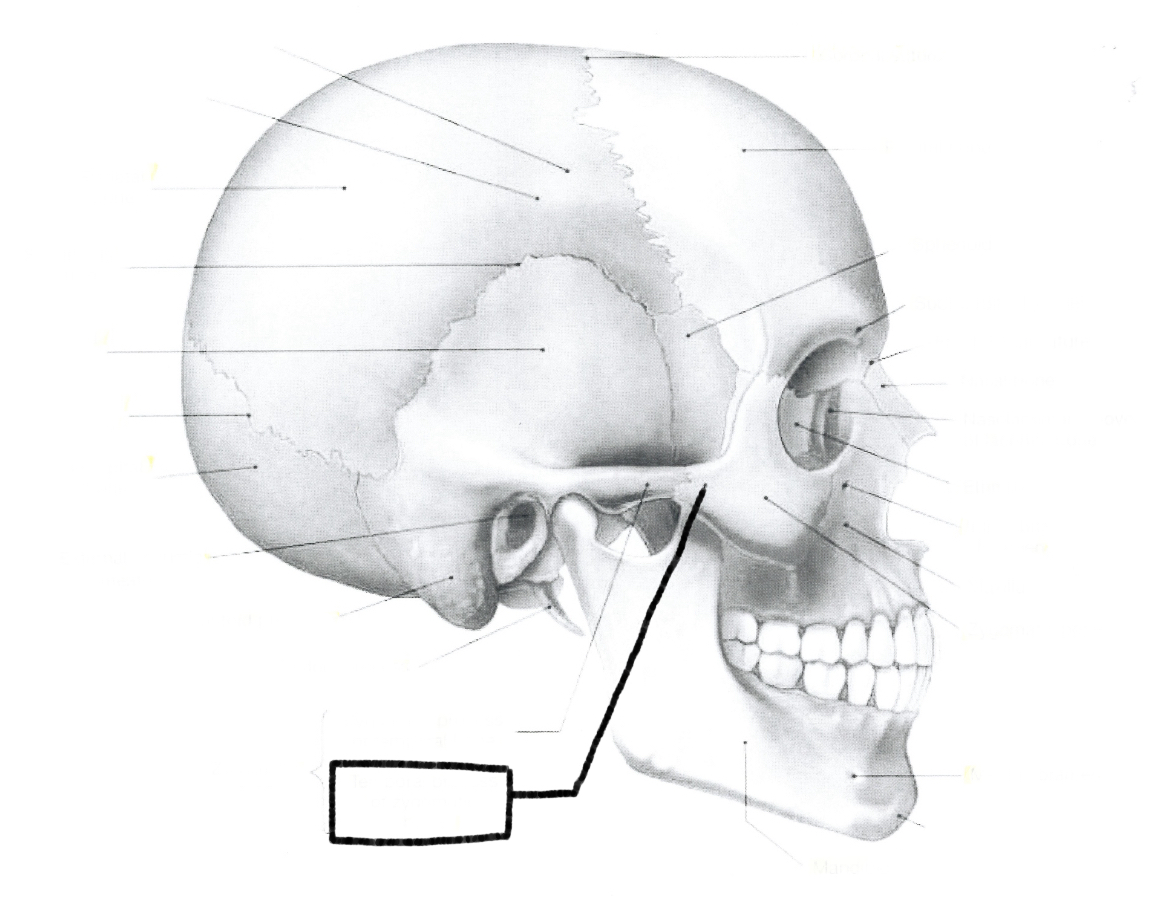

What is this?

Temporal process of zygomatic zone